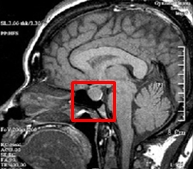

뇌하수체 양성 및 악성 신생물(Malignant or benign neoplasm of Pituitary gland)

- 증상

유루증,

불임,

성선 기능 저하증,

두통,

질의 건조함,

성욕감퇴,

시야장애,

생리불순

- 관련질환

-

쿠싱 증후군,

뇌하수체 기능부전,

대뇌성 거인증 ,

프라더 윌리 증후군 ,

뇌하수체 기능 항진,

뇌하수체의 악성 신생물

- 진료과

내분비내과,

방사선종양학과,

신경외과,

소아신경외과